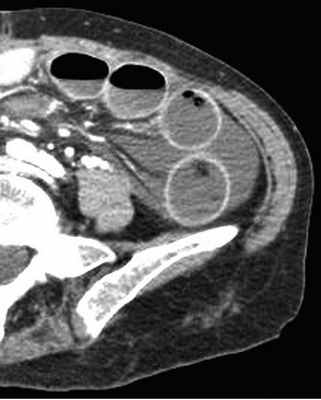

Декомпенсированная форма

Определяются все признаки, описанные при простой форме, дополнительно появляются патологические изменения в брюшной полости:

-расширенные петли тонкой кишки проксимальнее транзиторной зоны (зоны обструкции);

-спавшиеся петли кишечника дистальнее уровня обструкции;

-нормальные не утолщённые стенки кишечника с гомогенным одинаковым контрастным усилением;

-свободная жидкость между расширенными петлями кишечника, зачастую в виде пикантной детали женского туалета-трусиков танга, поэтому в многих источниках описывается как признак "танга" (tanga sign);

-свободная жидкость в брыжеечных карманах;

-свободная жидкость в брюшной полости.

Примеры скопления жидкости между петлями кишечника (танга) и в карманах брыжейки при декомпенсированной форме.